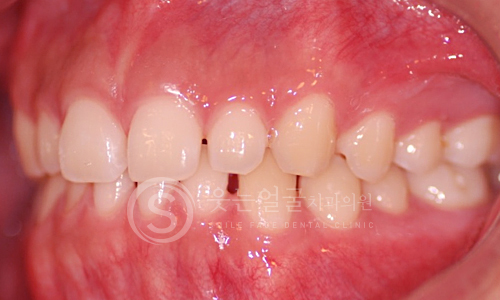

한눈에 보는

임플란트 전후사진